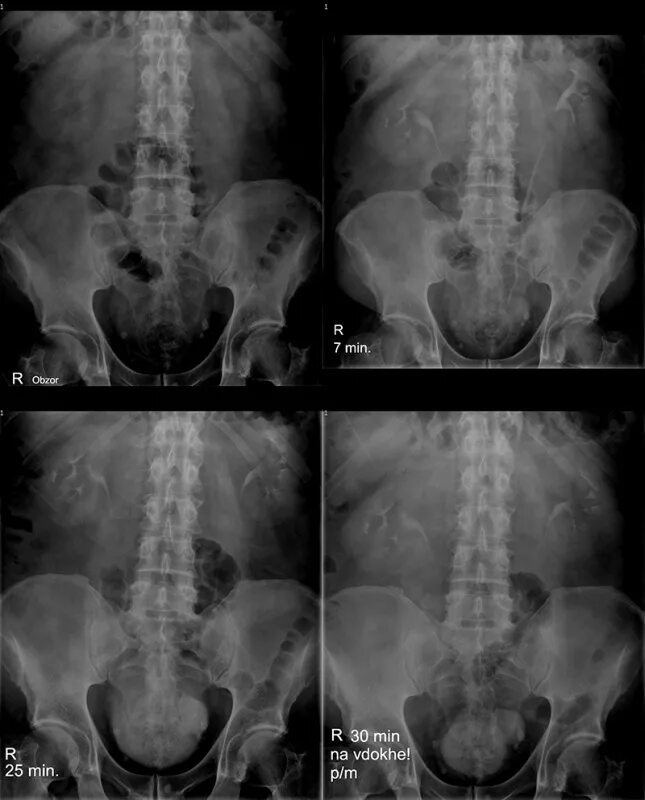

После урографии